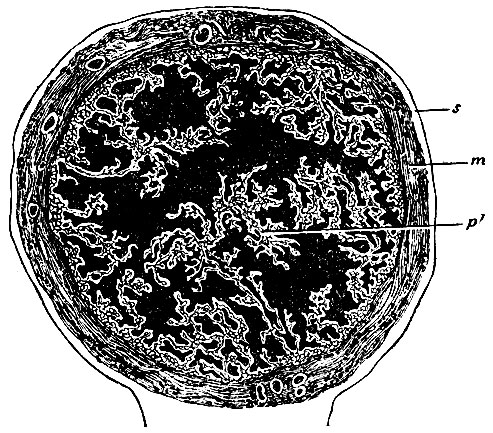

Стенки фаллопиевых труб состоят из тех же элементов, что и стенки матки, продолжение которой они представляют. Наружная оболочка есть серозный листок широкой связки, который, обогнув трубу со всех сторон, прикрепляет ее на верхнем краю связки. Покров этот продолжается до самого конца фимбрий, где сходится со слизистой оболочкой, выстилающей внутреннюю поверхность последних. Второй слой - мышечный - представляет продолжение подсерозного и по преимуществу надсосудистого слоя мышечной стенки матки. Большинство волокон его расположены кольцеобразно: продольные волокна, лежащие снаружи круговых, не многочисленны. Слизистая оболочка, представляющая продолжение слизистой оболочки матки, тем не менее резко от нее отличается, как по внешнему виду, так и по строению. Во всю длину трубы слизистая оболочка образует продольные складки, которые в интерстициальной и средней частях довольно правильны и прямы, в широкой же части достигают очень значительной высоты и принимают весьма сложную форму, так что на поперечном разрезе имеют вид ветвистых растений и своими разветвлениями почти выполняют просвет трубы (рис. 258). Продолжаясь на фимбрий, складки слизистой оболочки придают их внутренней поверхности морщинистый вид, а узкому отверстию воронки (конец фаллопиевой трубы) - звездообразную форму. Строение слизистой оболочки фаллопиевых труб отличается главным образом тем, что эпителий в трубе становится мерцательным (т. е. снабжен протоплазматическими тонкими отростками, которые находятся в постоянном движении), что чрезвычайно важно для механизма прохождения по трубе яиц.

Рис. 258. Поперечный разрез фаллопиевой трубы (увеличенный). s - серозная оболочка; m - мышечная оболочка; pl - слизистая оболочка, образующая высокие и ветвистые складки